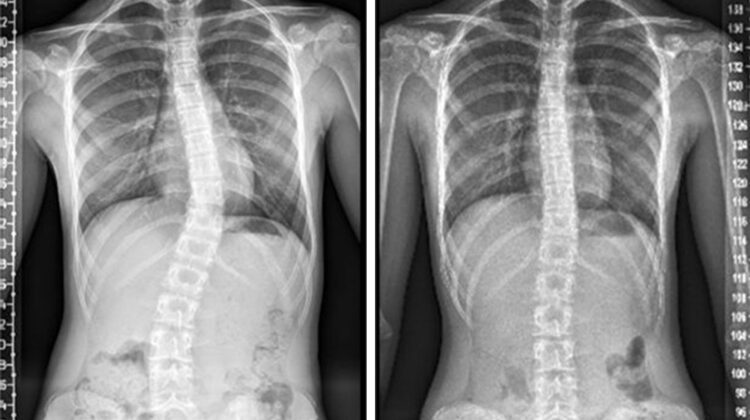

يطرح كثير من الأهل والمرضى سؤالًا مهمًا: هل يمكن علاج الجنف بدون عملية جراحية؟ والإجابة المختصرة هي: نعم، في عدد كبير من الحالات يمكن التحكم في الجنف، أو إيقاف تطوره، أو حتى تحسين شكله ووظيفته بدون جراحة. ومع ذلك، يعتمد القرار الصحيح على فهم نوع الجنف، ودرجة الانحناء، ومرحلة النمو، وطريقة المتابعة والعلاج. في هذا المقال، نشرح الحقيقة الكاملة بلغة بسيطة، ونجيب عن الأسئلة التي تدور في ذهن الأسرة، مع توضيح الخيارات غير الجراحية المتاحة اليوم.

الجنف، أو اعوجاج العمود الفقري، هو انحراف جانبي مصحوب بدوران في الفقرات، وقد يظهر في الطفولة أو المراهقة أو حتى عند البالغين. يختلف مسار الحالة من شخص لآخر؛ فبعض الانحناءات تبقى بسيطة وثابتة، بينما قد تتطور أخرى مع النمو. لذلك، لا يمكن تعميم قرار الجراحة أو استبعاده دون تقييم شامل.

في هذه الحالات، يهدف العلاج إلى تقليل الانحناء، وتحسين التوازن العضلي، وتقليل الألم، وتحسين المظهر الوظيفي للجسم.

نعم، في نسبة كبيرة من الحالات يمكن علاج الجنف بدون عملية أو على الأقل السيطرة عليه ومنع تطوره. يعتمد النجاح على: